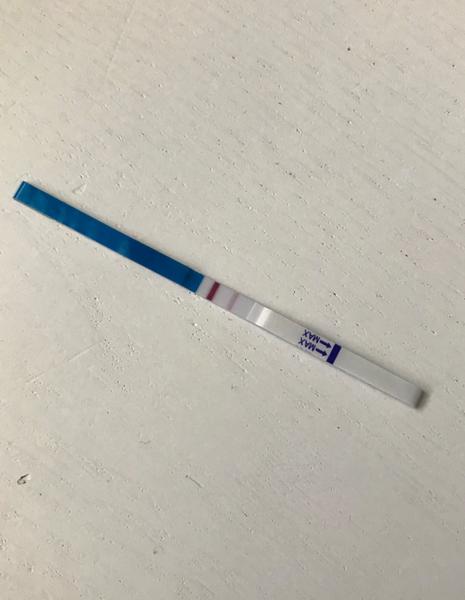

Test v den očekávané ms. Je to duch?

@rulexnone no krása gratuluji ♥ ♥ já dneska takto 😀 13 dnů od ovitrelle,12 dnů od IUI a 11DPO ♥ ve skutečnosti to už je reguální čárka ♥

@rulexnone asi taková jakou jsi měla včera ♥ ♥ ms mi nemá dojít za 3 nebo 4 dny ♥ ♥ ♥

@rulexnone Určitě bych testovala za 2 dny z ranní moči. Pokud bude sílit, je vše na dobré cestě 🙂 také jsem to tak měla a teď jsem 6+3